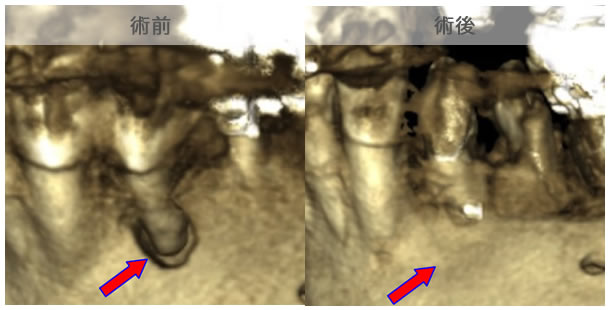

頬側骨壁の根尖部まで無くなっています。

MTA根充後11ヶ月で透過像が消失し、根尖部が正常化しました。

頬側骨の喪失が見られましたが17ヶ月で回復しました。

頬側骨の回復が確認できます。

| 治療説明 | 左下第一小臼歯の頬側根尖部からの排膿、痛みはないそうです。X線画像では根尖部に透過像を認められます。 頬側の骨も失われており、歯髄が死んだことが原因と考えられます。修復物を除去後根管治療を行い、根管充填後、透過像は消失、頬側骨も再生されていました。 |